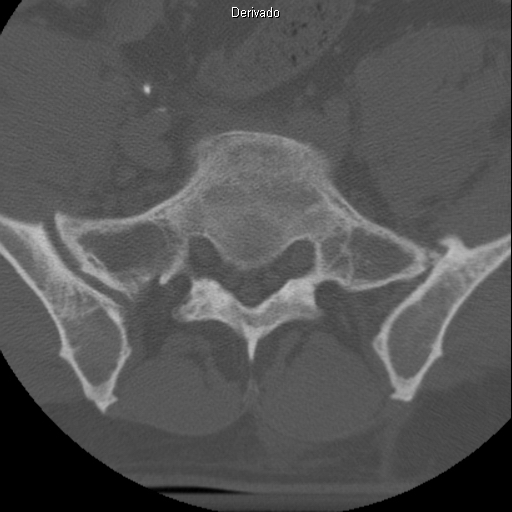

JANELA DE OSSO:

| Fractura da Apófise Transversa Esq. de L4 |

| Fractura Somática anterosuperior de L5. Envolvimento parcial do Pedículo Drt. |

| # Apófise articular sup. de L5 |

| Listese posterior de L5 sobre S1. #Apófise Espinhosa de L4 |

| Corte Coronal mostra # cominutiva da Faceta articular sup. Drt de L5 |